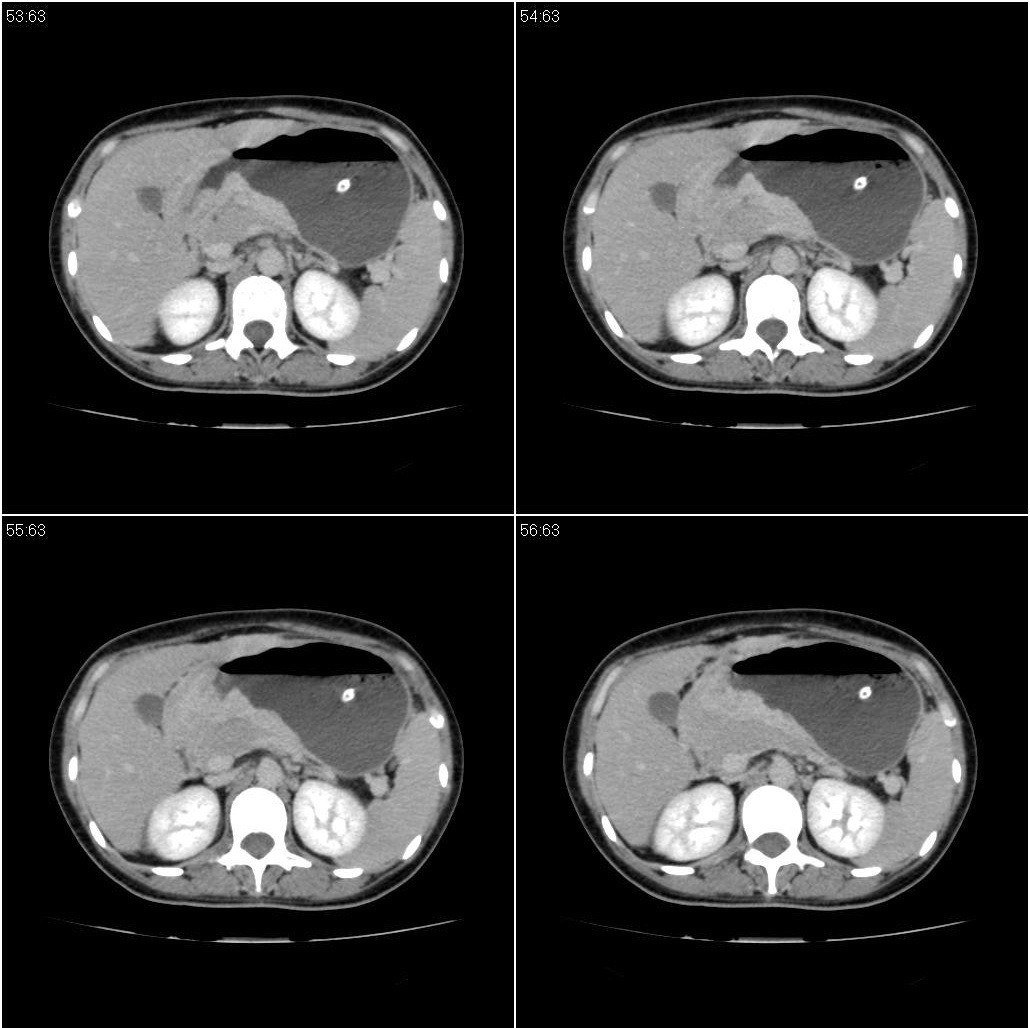

标题: CT21386:女性,33岁。4个月前因妊娠发现盆腔肿物。 [打印本页]

女性,33岁。4个月前因妊娠发现盆腔肿物。ca-125: 1100

胃幽门部癌伴小弯侧和腹腔淋巴结转移,胃内有胃管。

有明显淋巴结吗?我们感觉像是胰腺和胃窦。不过,胰腺尤其是胰头较大,不知道是否正常?

胃窦贲门胃小弯好像都厚啊 ,胃窦处比较明显,而且胃腔扩张明显,考虑胃癌伴梗阻。

胃壁局限性增厚,支持肿瘤性病变伴周围脓肿形成可能

未见明显肿大淋巴结,另肝脾大

高密度影是胃肠减压的管子。

支持;胃癌【浸润】幽门梗阻.胰头、胆囊及肝左叶受侵,副脾.

考虑胃窦占位并肝门部淋巴结转移

考虑胃窦部胃癌伴小弯侧和腹腔淋巴结转移。